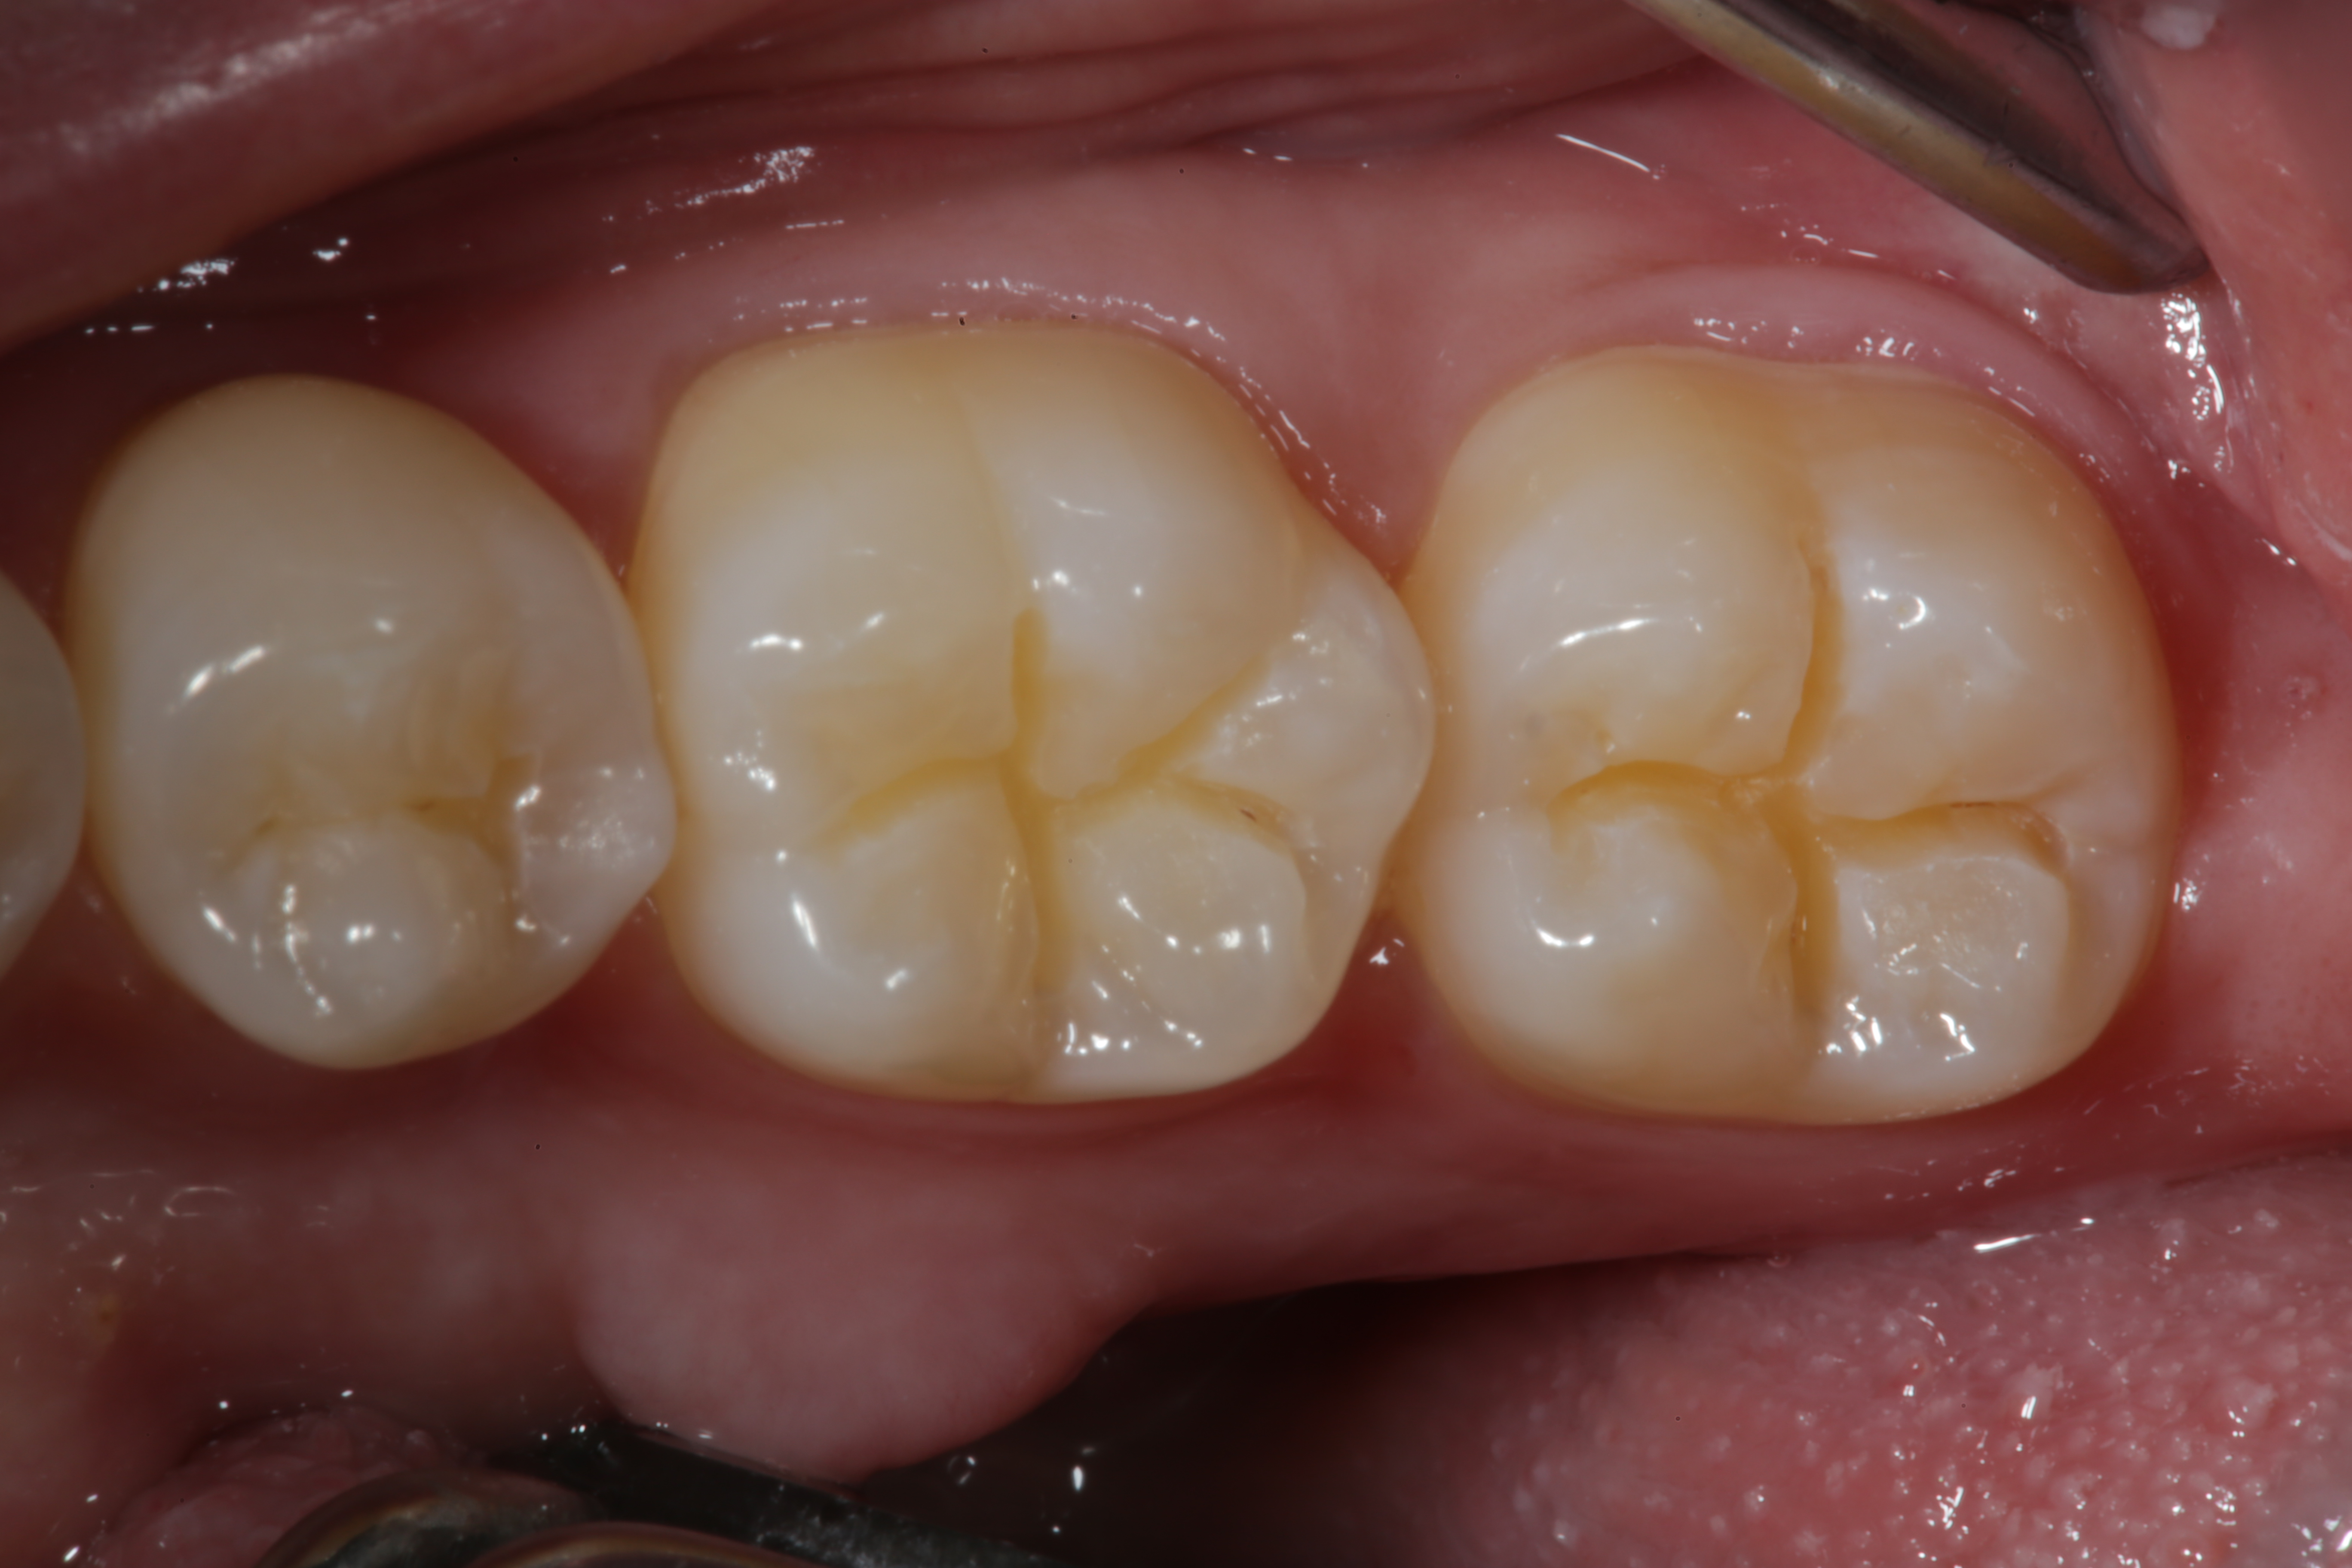

Fig 1. An occlusal view of teeth Nos. 29, 30, and 31 after micro-preparation with a Fissurotomy bur to remove decay diagnosed by quantitative light fluorescence (QLF).

Figure 1

Fig 6. An occlusal view of the completed micro-preparations on the occlusal surfaces of teeth Nos. 29, 30, and 31 restored with Giomer flowable composite.

Figure 6